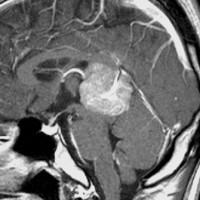

この例は古いので第3脳室開窓術 ETV をしていません。左はICE化学療法前。中央は9日後。右は25日後です。閉塞性水頭症があっても1週間くらいで中脳水道が通って水頭症は改善します。ジャーミノーマであれば,ICE化学療法1コースでかなり縮小するはずです。このような顕著な効果がない時には,逆にジャーミノーマ以外の胚細胞腫瘍が混在していると考えた方がいいでしょう。多くは奇形腫の混在です。